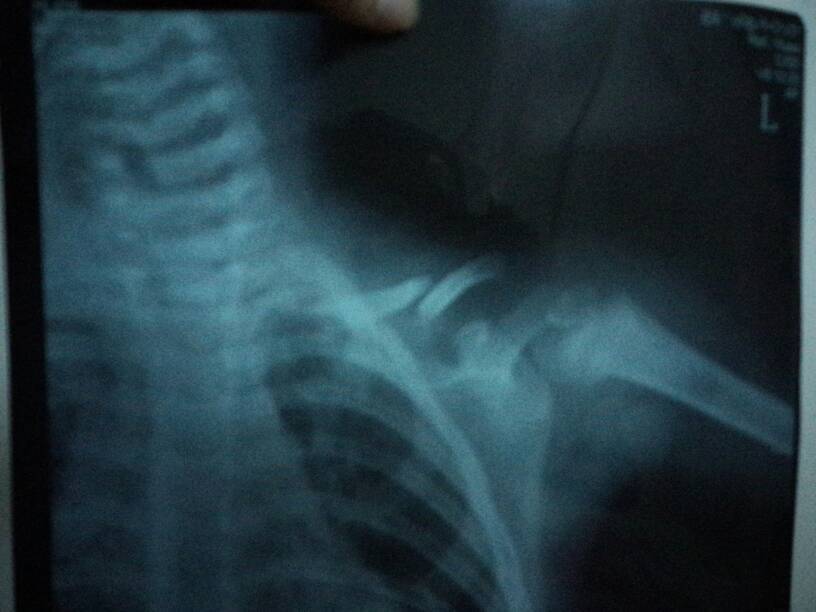

小孩一岁半,不小心将左肩摔骨折(下面有图),到四川华西医院挂急诊,医生说用背背佳就可以,一星期后复查,复查时说不行了,要做手术用钢板固定,去住院部问,没有床位,做不了手术,求医生给建议,医生建议去四川省医院,省医院医生说没事,就用背背佳固定就可以了,我们现在很困惑,到底是做手术好,还是背背佳固定自己复原的好!求有经验的医生朋友或者有相同经历的父母给点建议,谢谢了!